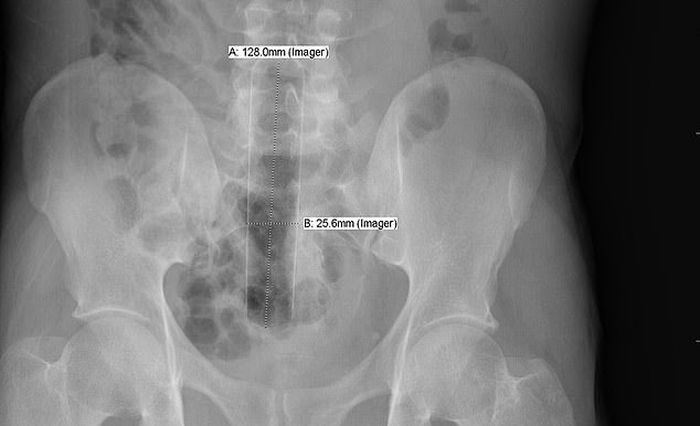

Դանակ, պատառաքաղ, մանկական խաղալիքներ ու գարեջրի շշեր: Այս ամենն ինչ-որ ձևով կարող է հայտնվել օրգանիզմում: Այս նկարները նայելիս կարող եք համոզվել, որ այս կյանքում ամեն ինչ հնարավոր է: